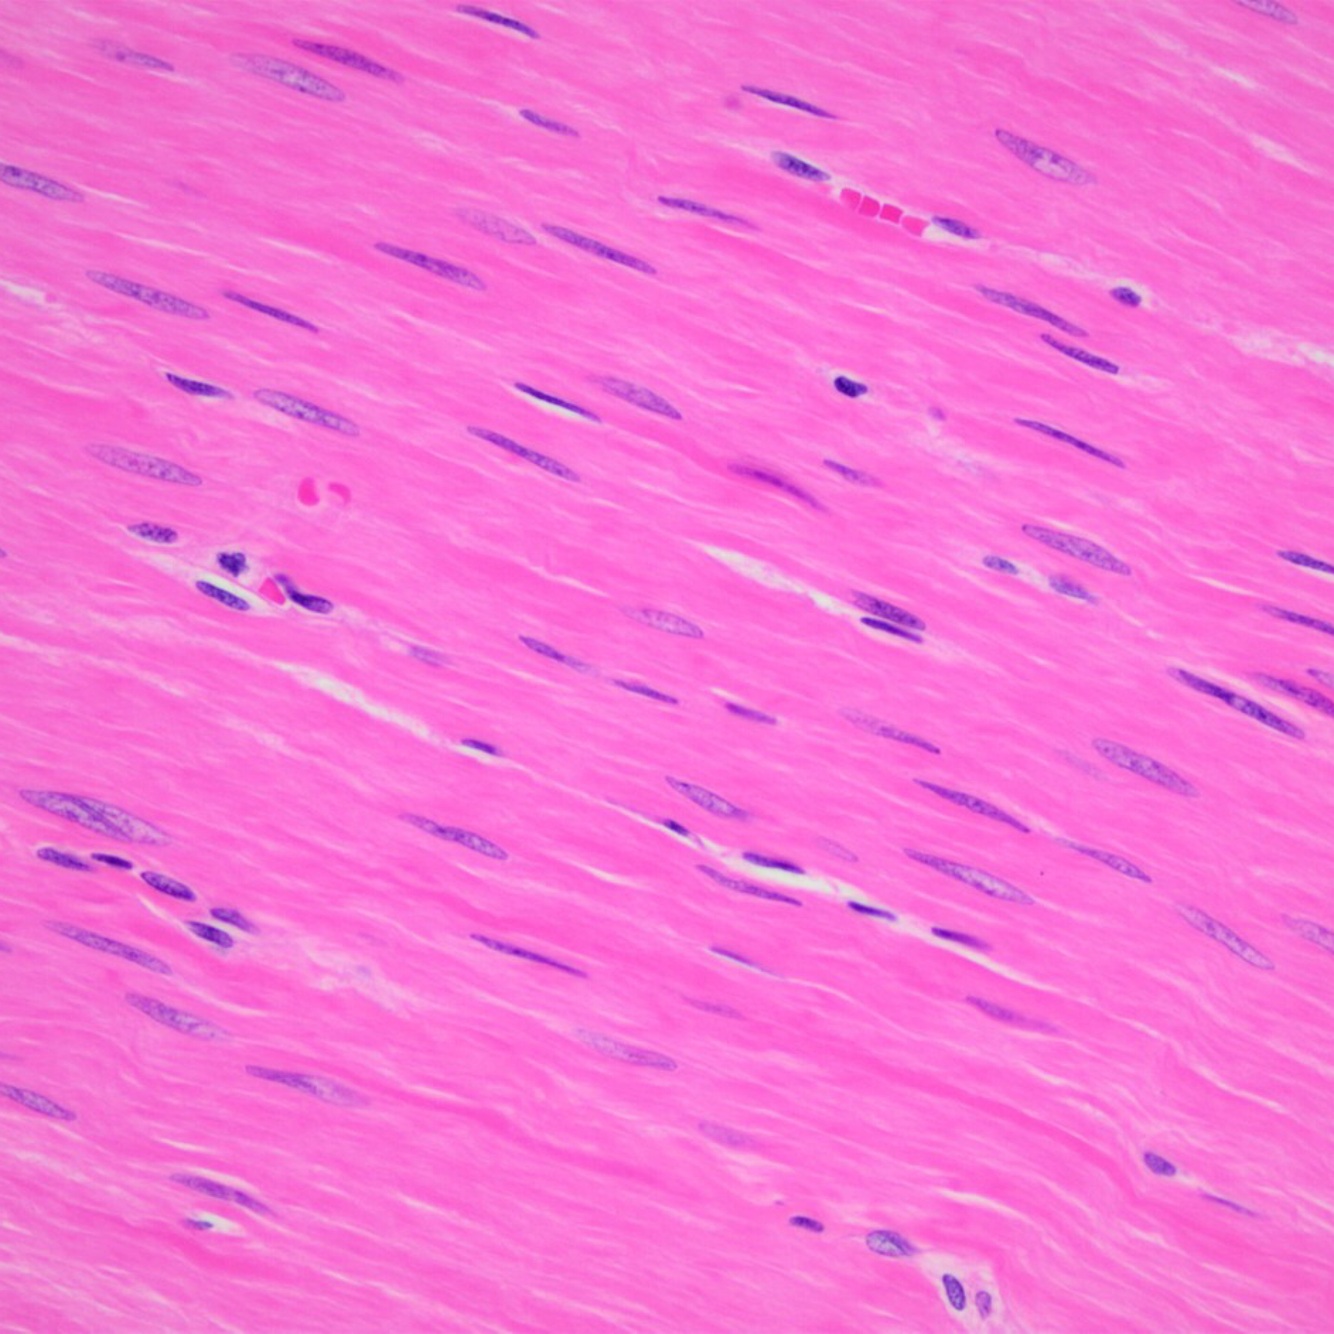

Q

ID the muscle tissue

A

Smooth Muscle tissue